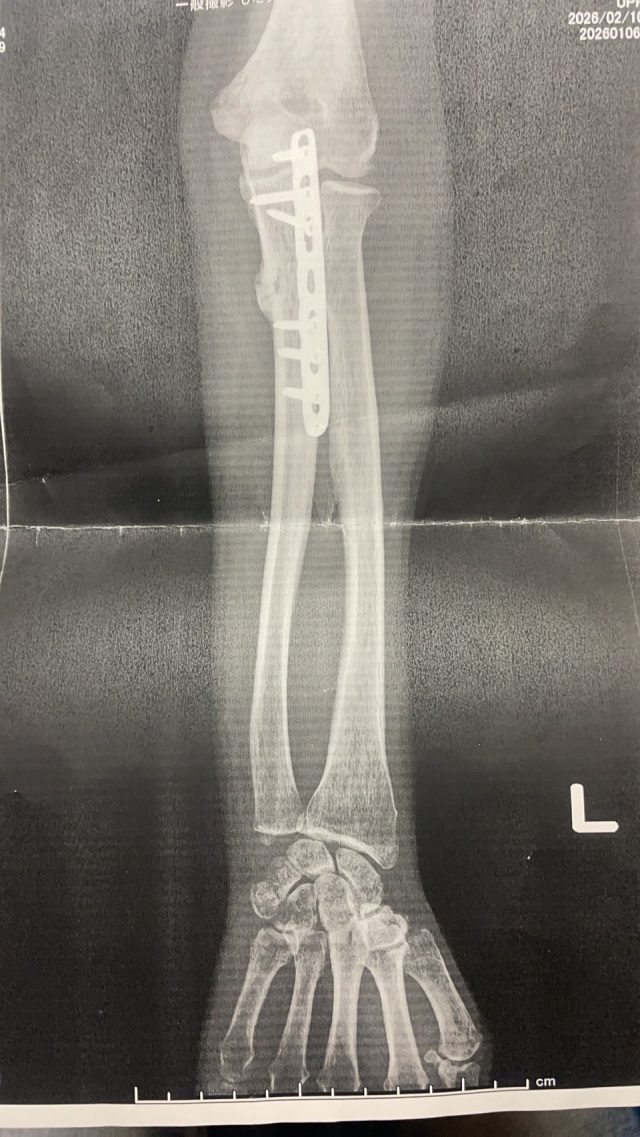

実際のレントゲン写真です。 ※掲載の許可はいただいております

実際の患者さんの写真です。 これは実際に来院された方のレントゲン写真です。 骨折後の影響で、関節の動きが制限されています